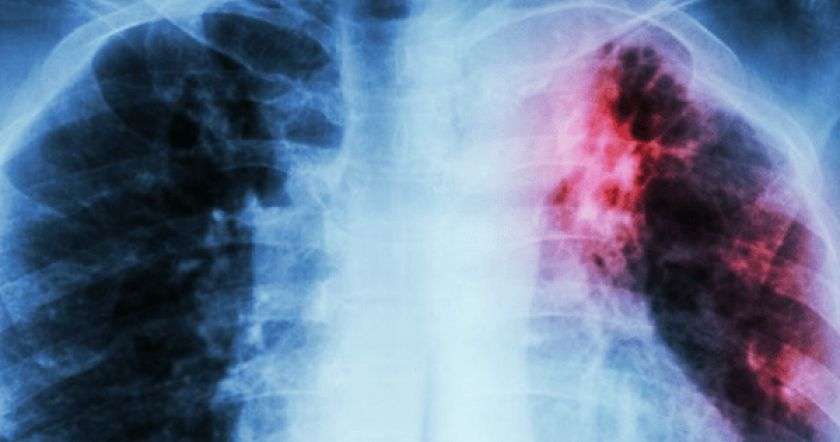

Курение — одна из самых вредных привычек, которую вы можете иметь, так как она серьезно повреждает здоровье и приводит к различным заболеваниям.

Сигаретный дым вызывает серьезное и необратимое повреждение легких, поэтому мы настоятельно рекомендуем вам отказаться от курения, никогда не поздно.